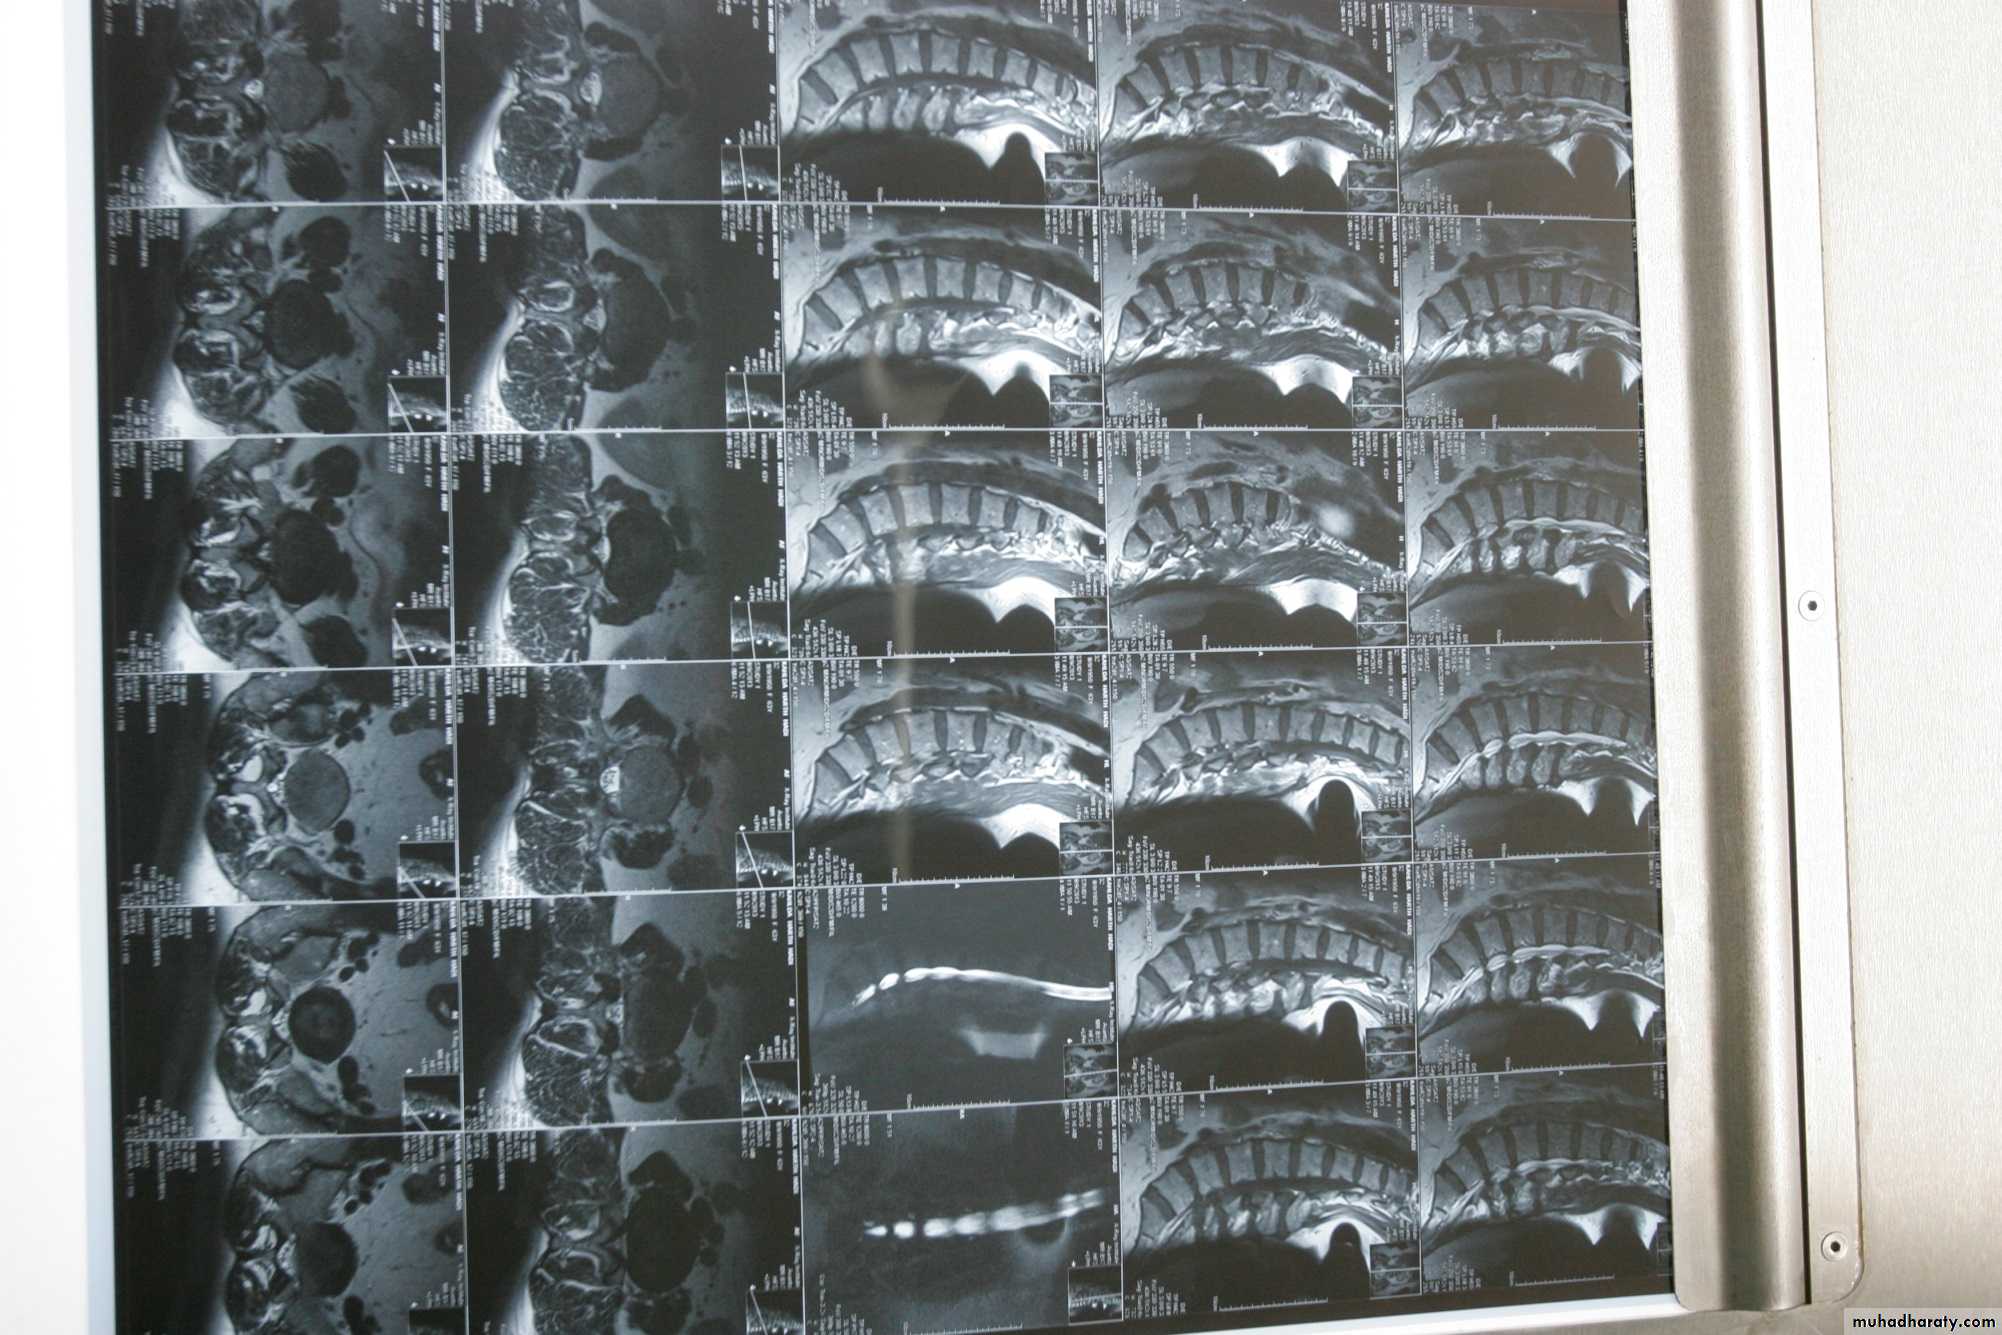

MRI

It is superior to computed tomography (CT) because of its tissue contrast and multi planar capabilities.General objectives of treatment